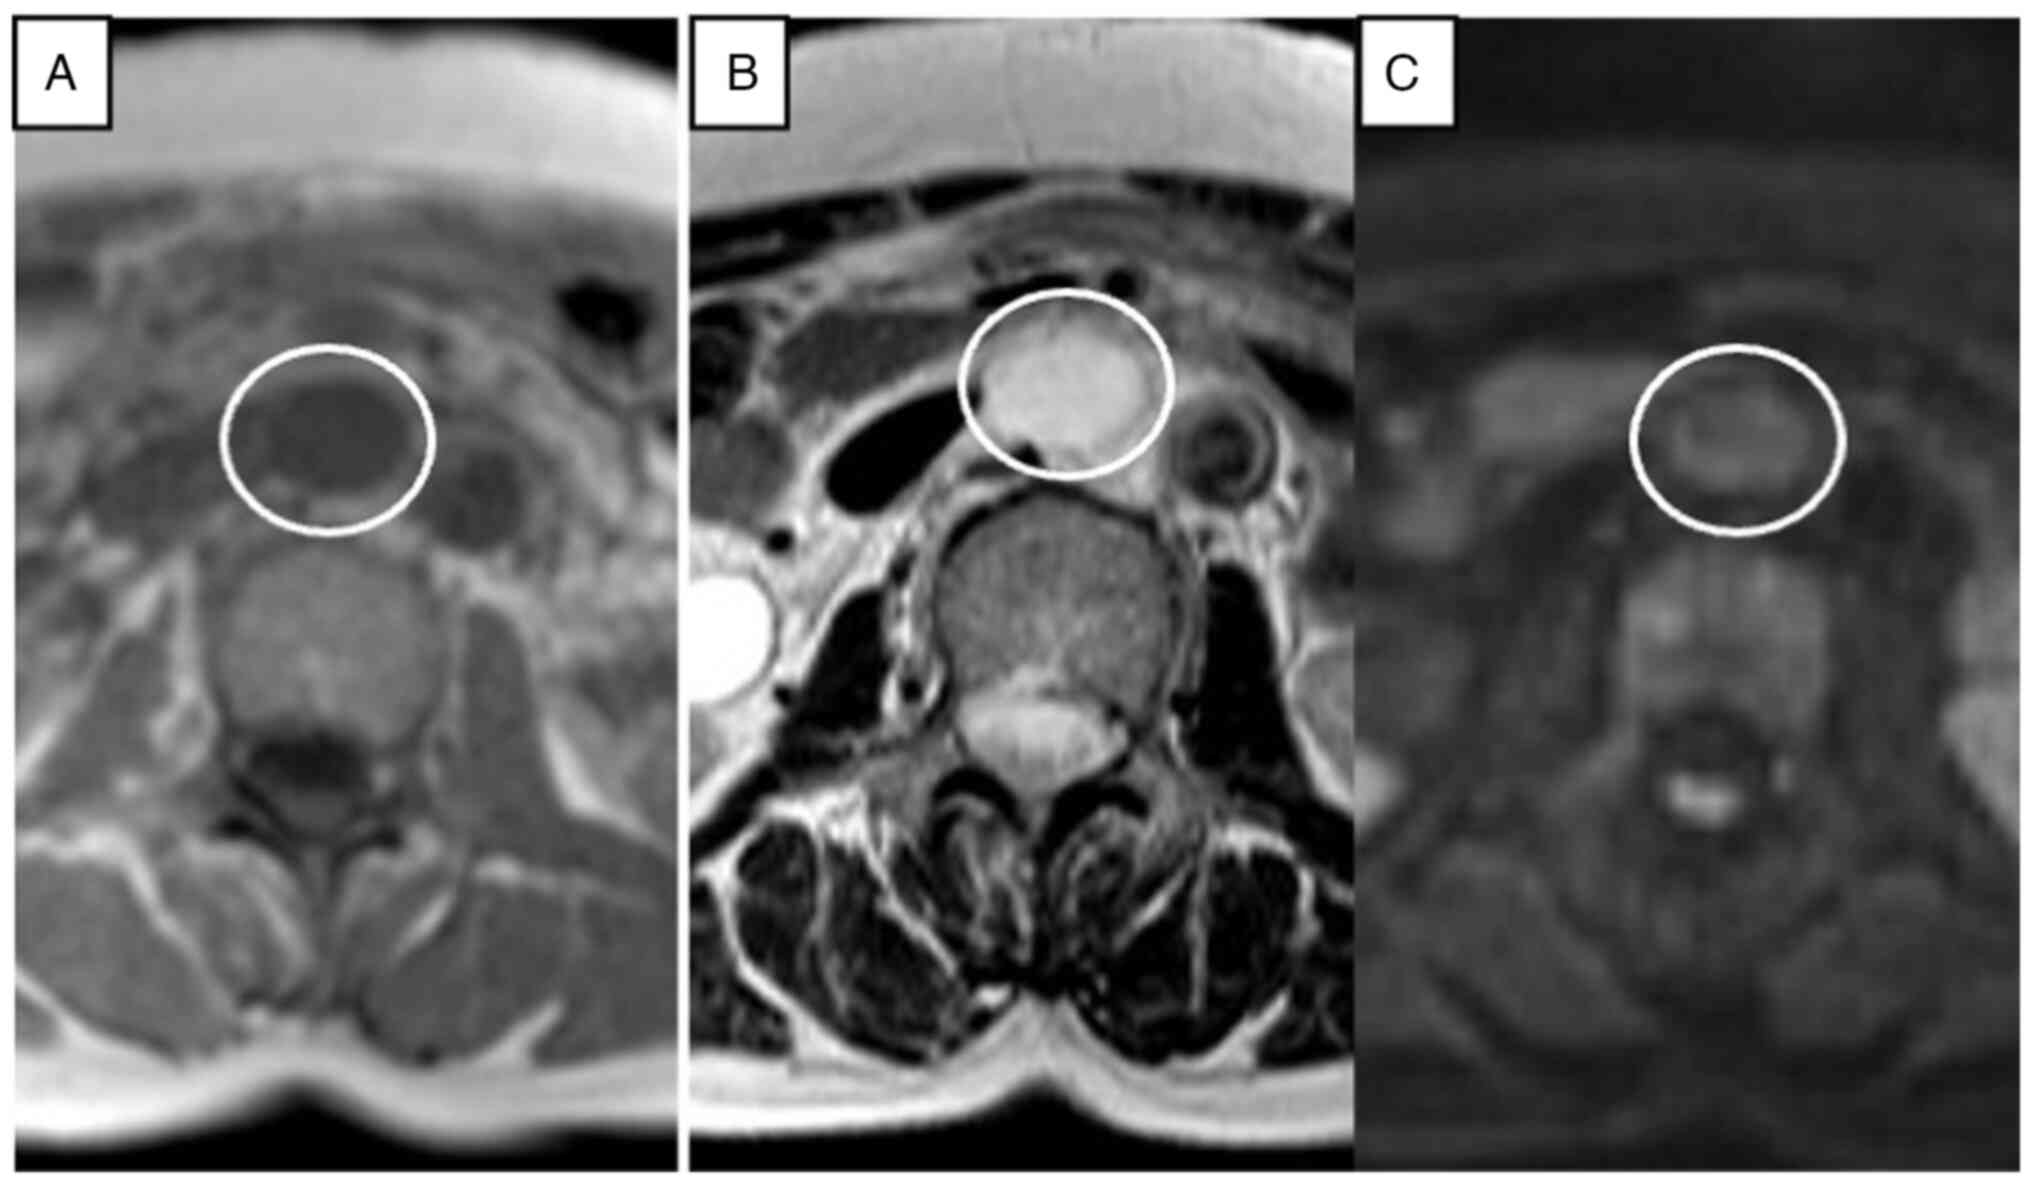

Anastomosing hemangioma (AH) is rare and a newly recognized variant of capillary hemangioma that is mostly found in the genitourinary tract. Additionally, AH is sometimes difficult to diagnose without pathological specimens. It is difficult to diagnose preoperatively due to the lack of specific clinical and radiologic appearance. The present report describes the imaging features from a radiological perspective and outlines the clinicopathologic features and treatment options. A 67‑year‑old woman was referred to Dokkyo Medical University Saitama Medical Center (Koshigaya, Japan) for a retroperitoneal tumor that was identified at a medical checkup 4 years prior. The patient had no symptoms, no abnormal physical signs and no past medical or specific family history. Routine blood tests were all within the normal ranges. A nonenhanced CT scan showed a circular, homogenous, well‑circumscribed retroperitoneal tumor that was ~32x23 mm in size, between the abdominal aorta and the inferior vena cava, and just below the left renal vein. On a contrast‑enhanced multidetector CT scan, the tumor showed heterogeneous septal enhancement in the arterial phase and persistent enhancement in the portal phase. The tumor was diagnosed as a benign neurogenic tumor or a retroperitoneal cavernous hemangioma at the time, and the patient was intended to be followed up at the outpatient clinic. However, it gradually increased to a maximum diameter of 35 mm over 4 years. Finally, it was completely resected by open laparotomy and pathologically diagnosed as AH. Retroperitoneal hemangioma is extremely rare in adulthood and has been confirmed in only 1‑3% of all retroperitoneal tumors. To the best of our knowledge, only 6 cases of para‑aortic AH have been reported. The incidence of this variant is very low. However, AH may be included in the differential diagnosis when a slowly progressing heterogeneous mass appears in the para‑aortic region that exhibits a CT‑enhanced pattern similar to a typical cavernous hemangioma.